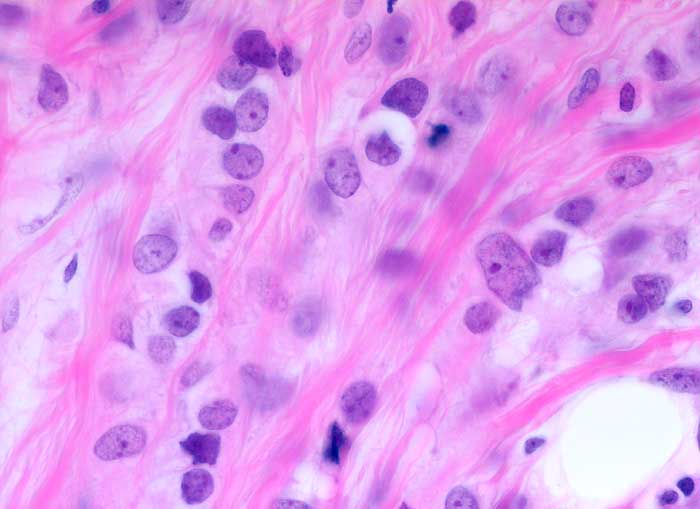

invasiv lobuläres Mammakarzinom

In Einerreihen hintereinander gänsemarschartig angeordnete monomorphe kleine Tumorzellen mit geringen Atypien.